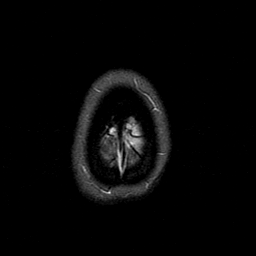

MR Study #1 -- Slice #49

[Home][Help][Clinical][Tour 1][Tour 2][Tour 3] Slice 49